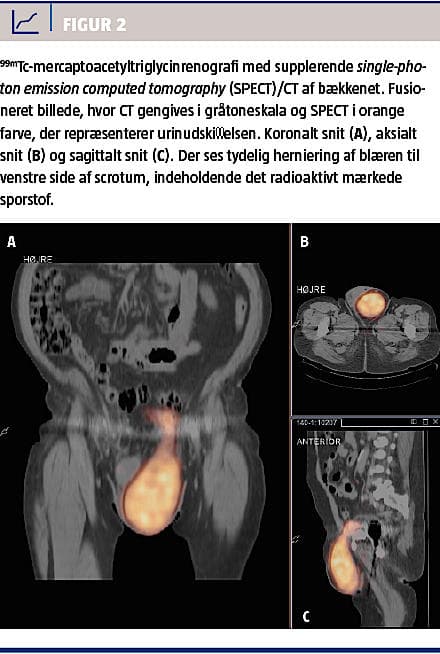

Han fik efterfølgende foretaget knoglescintigrafi pga. mistanke om løshed af en hofteprotese. Herved blev der påvist ophobning af det radioaktive sporstof i venstre del af scrotum og gav således mistanke om urinindhold i scrotum (Figur 1). Patienten blev indkaldt til renografi og single-photon emission computed tomography (SPECT)/CT (Figur 2). Renografien viste normal udskillelse i nyrerne uden tegn til afløbshindring. En dynamisk optagelse under miktion viste, at miktion kun var mulig ved kompression af venstre skrotalhalvdel. Ved kompression sås retrograd tømning af skrotalindhold til den suprapubisk beliggende blære og derefter til urethra. Yderligere viste CT med kontrast, at kun en lille del af blæren var beliggende i det lille bækken, mens størstedelen var beliggende i scrotum. Ved nærmere vandladningsanamnese fremgik det, at initiering af miktion altid skete ved tryk på scrotum, og at tømning skete ved at trykke scrotum tom. Ved flekscystoskopi sås en lille sammenfalden blære og en divertikelåbning med lumen på 2-3 cm, der førte ind i en stor skrotal divertikel.